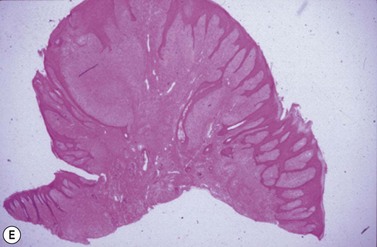

Pathology

Complex odontoma presents as a radiodense calcified lesion within the jaw of young horses. Grossly, they are very hard and difficult to prepare for histological examination. Cut surfaces reveal variegated cementum, dentin, and mineralized enamel (Fig. 11.10).34 The gross features are confirmed histologically, and there can be variable amounts of odontogenic epithelium. In the horse, there is plentiful cementum.

image

Fig. 11.10 Undecalcified thick section of a complex odontoma in a 2-year-old Morgan colt. Well-differentiated but disorganized components of tooth formation are shown. D, dentin; C, cementum; E, enamel.

(Reproduced with the kind permission of Dr R.R. Dubielzig and Iowa State Press.)

Compound odontoma presents as a similar lesion but radiographically shows several abnormal tooth-like structures (denticles) within the mass. Histological features are reminiscent of normal tooth development. In older lesions, epithelial tissue may be sparse.